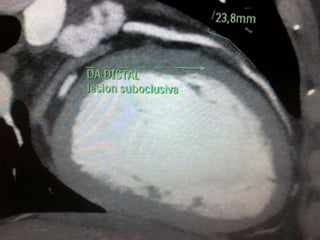

CASO CLINICO #3 MASCULINO 65 AÑOS DE EDAD DIABETES TIPO 2 DESDE HACE 15 AÑOS POBRE CONTROL METABOLICO DISLIPIDEMIA. OBESIDAD GRADO II. CUADRO CLINICO: ANGINA DE PECHO ATIPICA. CHEQUEO DE RUTINA. ECG DE REPOSO NORMAL. PRUEBA DE ESFUERZO POSITIVA Y PRECOZ PARA ISQUEMIA. TA 120/ 68 mm Hg. FC 67/min Fr 13/ min Glucosa en Ayunas 215 mg /dL. Colesterol total 260 mg/dL, LDL 135 mg d/L Creatinina 1.2 mg/dL EXAMEN FISICO ANODINO